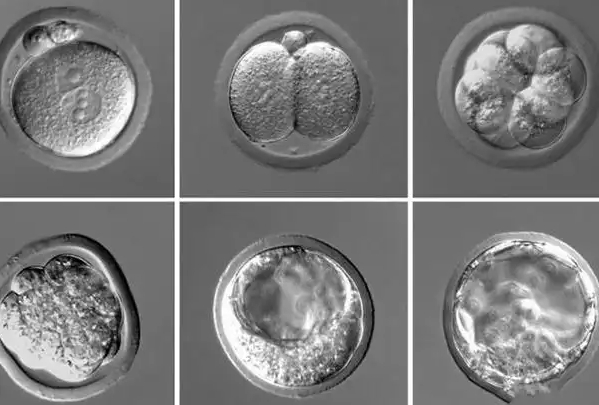

囊胚发育的基本过程

受精卵在体外培养5-6天后会发育成囊胚。这个阶段的胚胎已经形成两种明显不同的细胞群:内细胞团和滋养层细胞。内细胞团将来发育成胎儿,滋养层细胞则形成胎盘等支持组织。囊胚还会形成一个充满液体的腔体,称为囊胚腔。囊胚的扩张程度、内细胞团和滋养层细胞的质量共同决定了其等级评分。